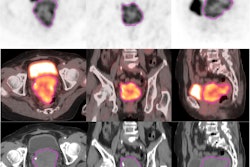

Jeong and colleagues conducted a study that included 252 locally advanced cervical cancer patients who underwent chemoradiotherapy between 2006 and 2019, dividing the group into training (167 patients) and test (85 patients) sets for a radiomics algorithm based on data from T1- and T2-weighted MR scans. The "handcrafted" radiomics model included 1,890 imaging features, while the deep-learning radiomics model consisted of a 3D convolutional neural network.